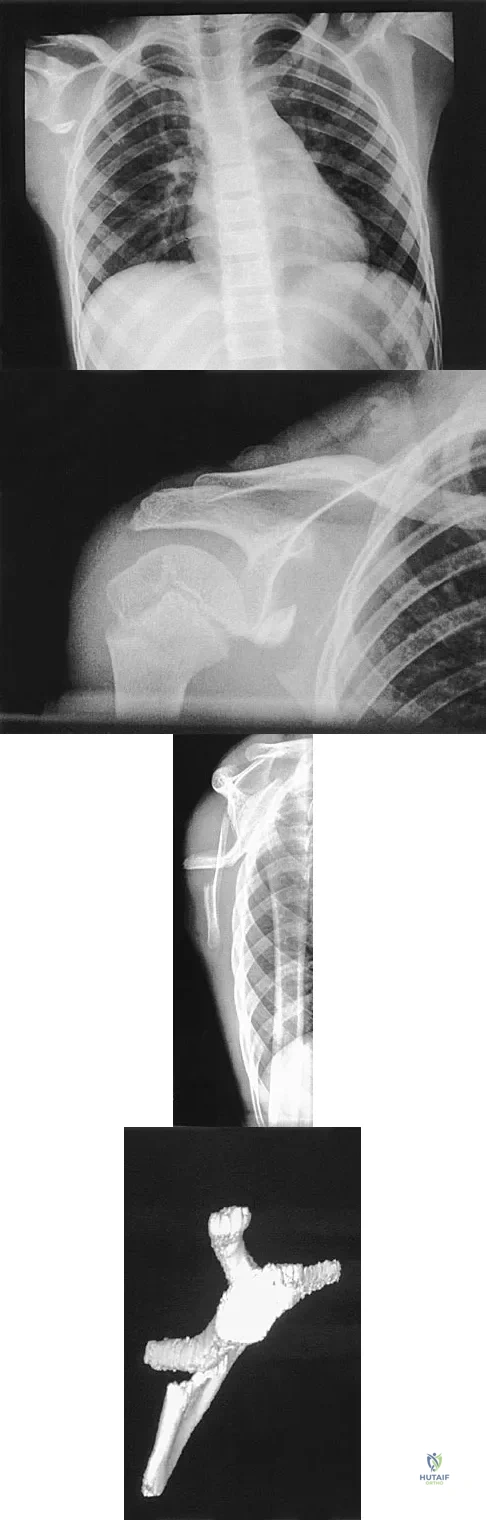

An otherwise healthy 75-year-old man has a painful mass in the popliteal fossa of his right knee. A lateral radiograph of the knee, a CT scan of the distal femur, and a histopathologic specimen are shown in Figures 13a through 13c. Management should consist of

Explanation